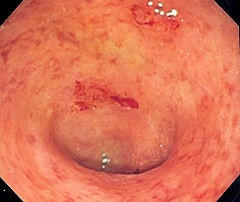

Неспецифический язвенный колит

Заболевание может начаться остро или развиваться постепенно. Все симптомы неспецифического язвенного колита обусловлены хроническим язвенно-воспалительным процессом в слизистой оболочке толстого кишечника. К ним относятся:

- Кашицеобразный стул или понос с примесью в каловых массах слизи, гноя и крови. Нередко у больных наблюдаются ложные и достаточно болезненные позывы к дефекации – тенезмы;